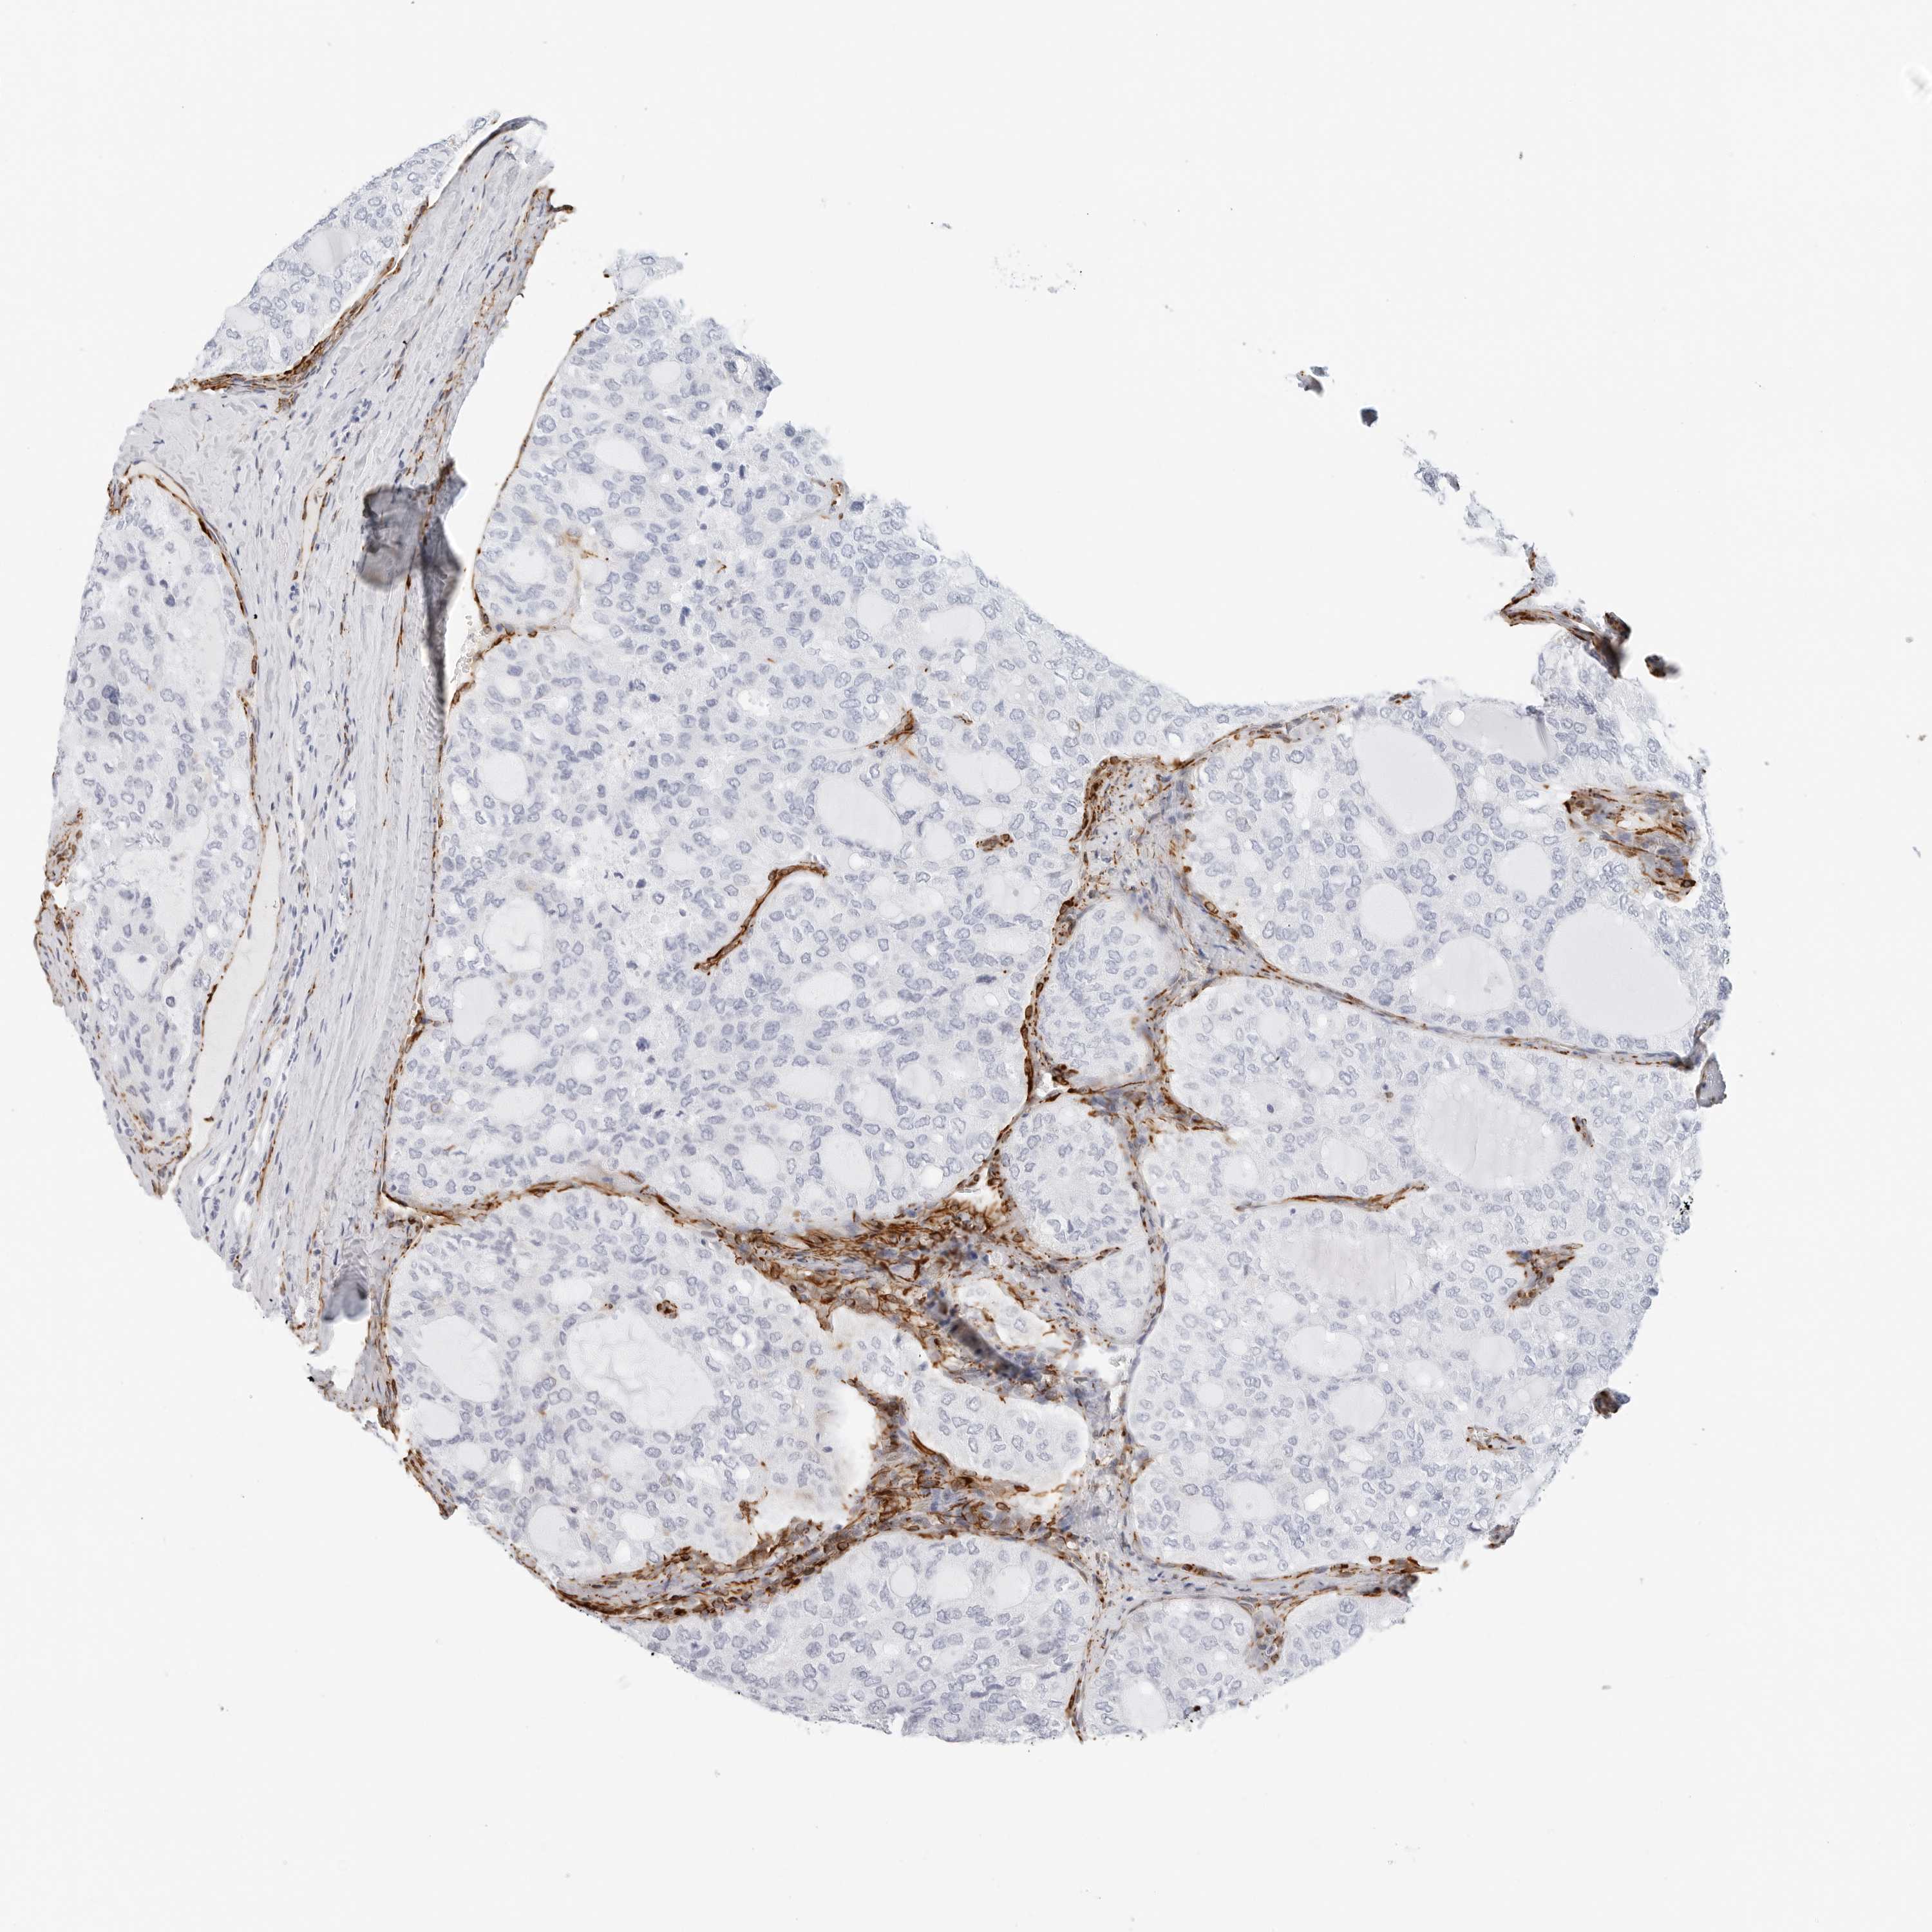

THYROID CANCER - Protein expressioni

A mouse-over function shows sample information and annotation data. Click on an image to view it in a full screen mode. Samples can be filtered based on level of antibody staining by selecting one or several of the following categories: high, medium, low and not detected. The assay and annotation is described here.

Note that samples used for immunohistochemistry by the Human Protein Atlas do not correspond to samples in the TCGA dataset.

Antibody stainingi

Antibody staining in the annotated cell types in the current human tissue is reported as not detected, low, medium, or high, based on conventional immunohistochemistry profiling in selected tissues. This score is based on the combination of the staining intensity and fraction of stained cells.

Each image is clickable and will lead to virtual microscopy that enables deeper exploration of all samples and also displays staining intensity scores, fraction scores and subcellular localization as well as patient and tissue information for each sample.

Antibody HPA007007

Antibody HPA026111

Antibody CAB005889

Antibody CAB058692

Staining

High

Medium

Low

Not detected

Intensity

Strong

Moderate

Weak

Negative

Quantity

>75%

75%-25%

<25%

None

Location

Nuclear

Cytoplasmic/membranous

Cytoplasmic/membranous,nuclear

Papillary adenocarcinoma, NOS

Follicular adenoma carcinoma, NOS